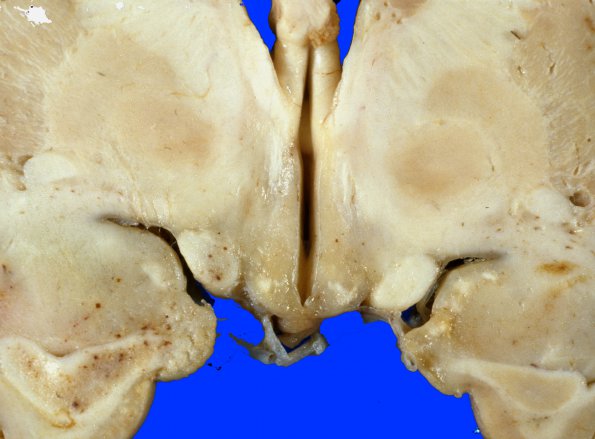

Necrotizing Leukoencephalopathy

4A3 MTX & Radiation (Case 4) Gross 12

Higher magnification of the third ventricle and associated structures.